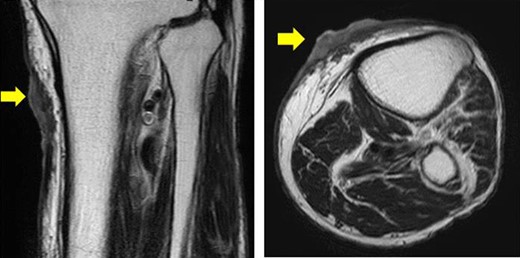

The patient was an 83-year-old male with a granulomatous tumor on his left lower leg. He said that it had existed for about 10 years. An incisional skin biopsy was performed at a neighbor medical institution and histopathologically suggested PCACC. He was introduced to our out-patient clinic. At his admission, the tumor was about 4 cm in the diameter and showed a few red granulomatous nodules (Fig. 1). MRI revealed that the tumor infiltrated subcutaneous tissue but did not reach muscle and bone (Fig. 2). The whole-body PET-CT showed that fluorodeoxyglucose (FDG) accumulated at the tumor area of the left lower leg. FDG also accumulated in the left inguen, however any other accumulation was not defected (Fig. 3). Therefore, it was suspected that the left inguinal hot spot was the metastatic lesion from the PCACC lesion at the left lower leg. At the first operation, the tumor was resected 2 cm far from the tumor margin, including basal muscle fascia and periosteum, and the defect was covered with an artificial dermis under general anesthesia (Fig. 4). At the same time, inguinal lymph node dissection was performed. Histopathological examination of the tumor revealed that cubical cells which had high nuclear-to-cytoplasmic ratio proliferated with cribriform, tubular or cord-like structure in the dermis and subcutaneous tissue. Perineural invasion by the tumor was observed. Metastasis to superficial inguinal lymph node was also histological confirmed (Figs 5 and 6). Most lumens had mucus which was stained by Alcian-blue (AL-B) and Periodic acid-Schiff (PAS) inside of them (Fig. 7). In the immunohistochemical findings, the tumor cells were positive for EMA, SMA, S-100protein, BerEP4, p63 and C-kit (Fig. 8). According to these clinical and pathological findings, the tumor was finally diagnosed the tumor as PCACC. Microscopically, the tumor was resected completely.

Horizontal and sagittal views on MRI T2 (yellow arrow indicates the tumor).